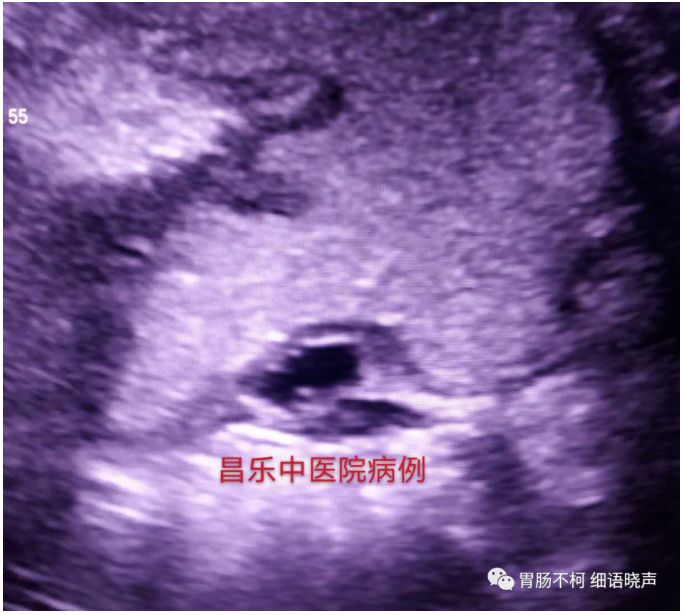

病例一:胃窦小弯侧可见黏膜下层来源扁盘状病灶,近胃腔面可见强-低-强三层回声,内部回声呈典型网格状。